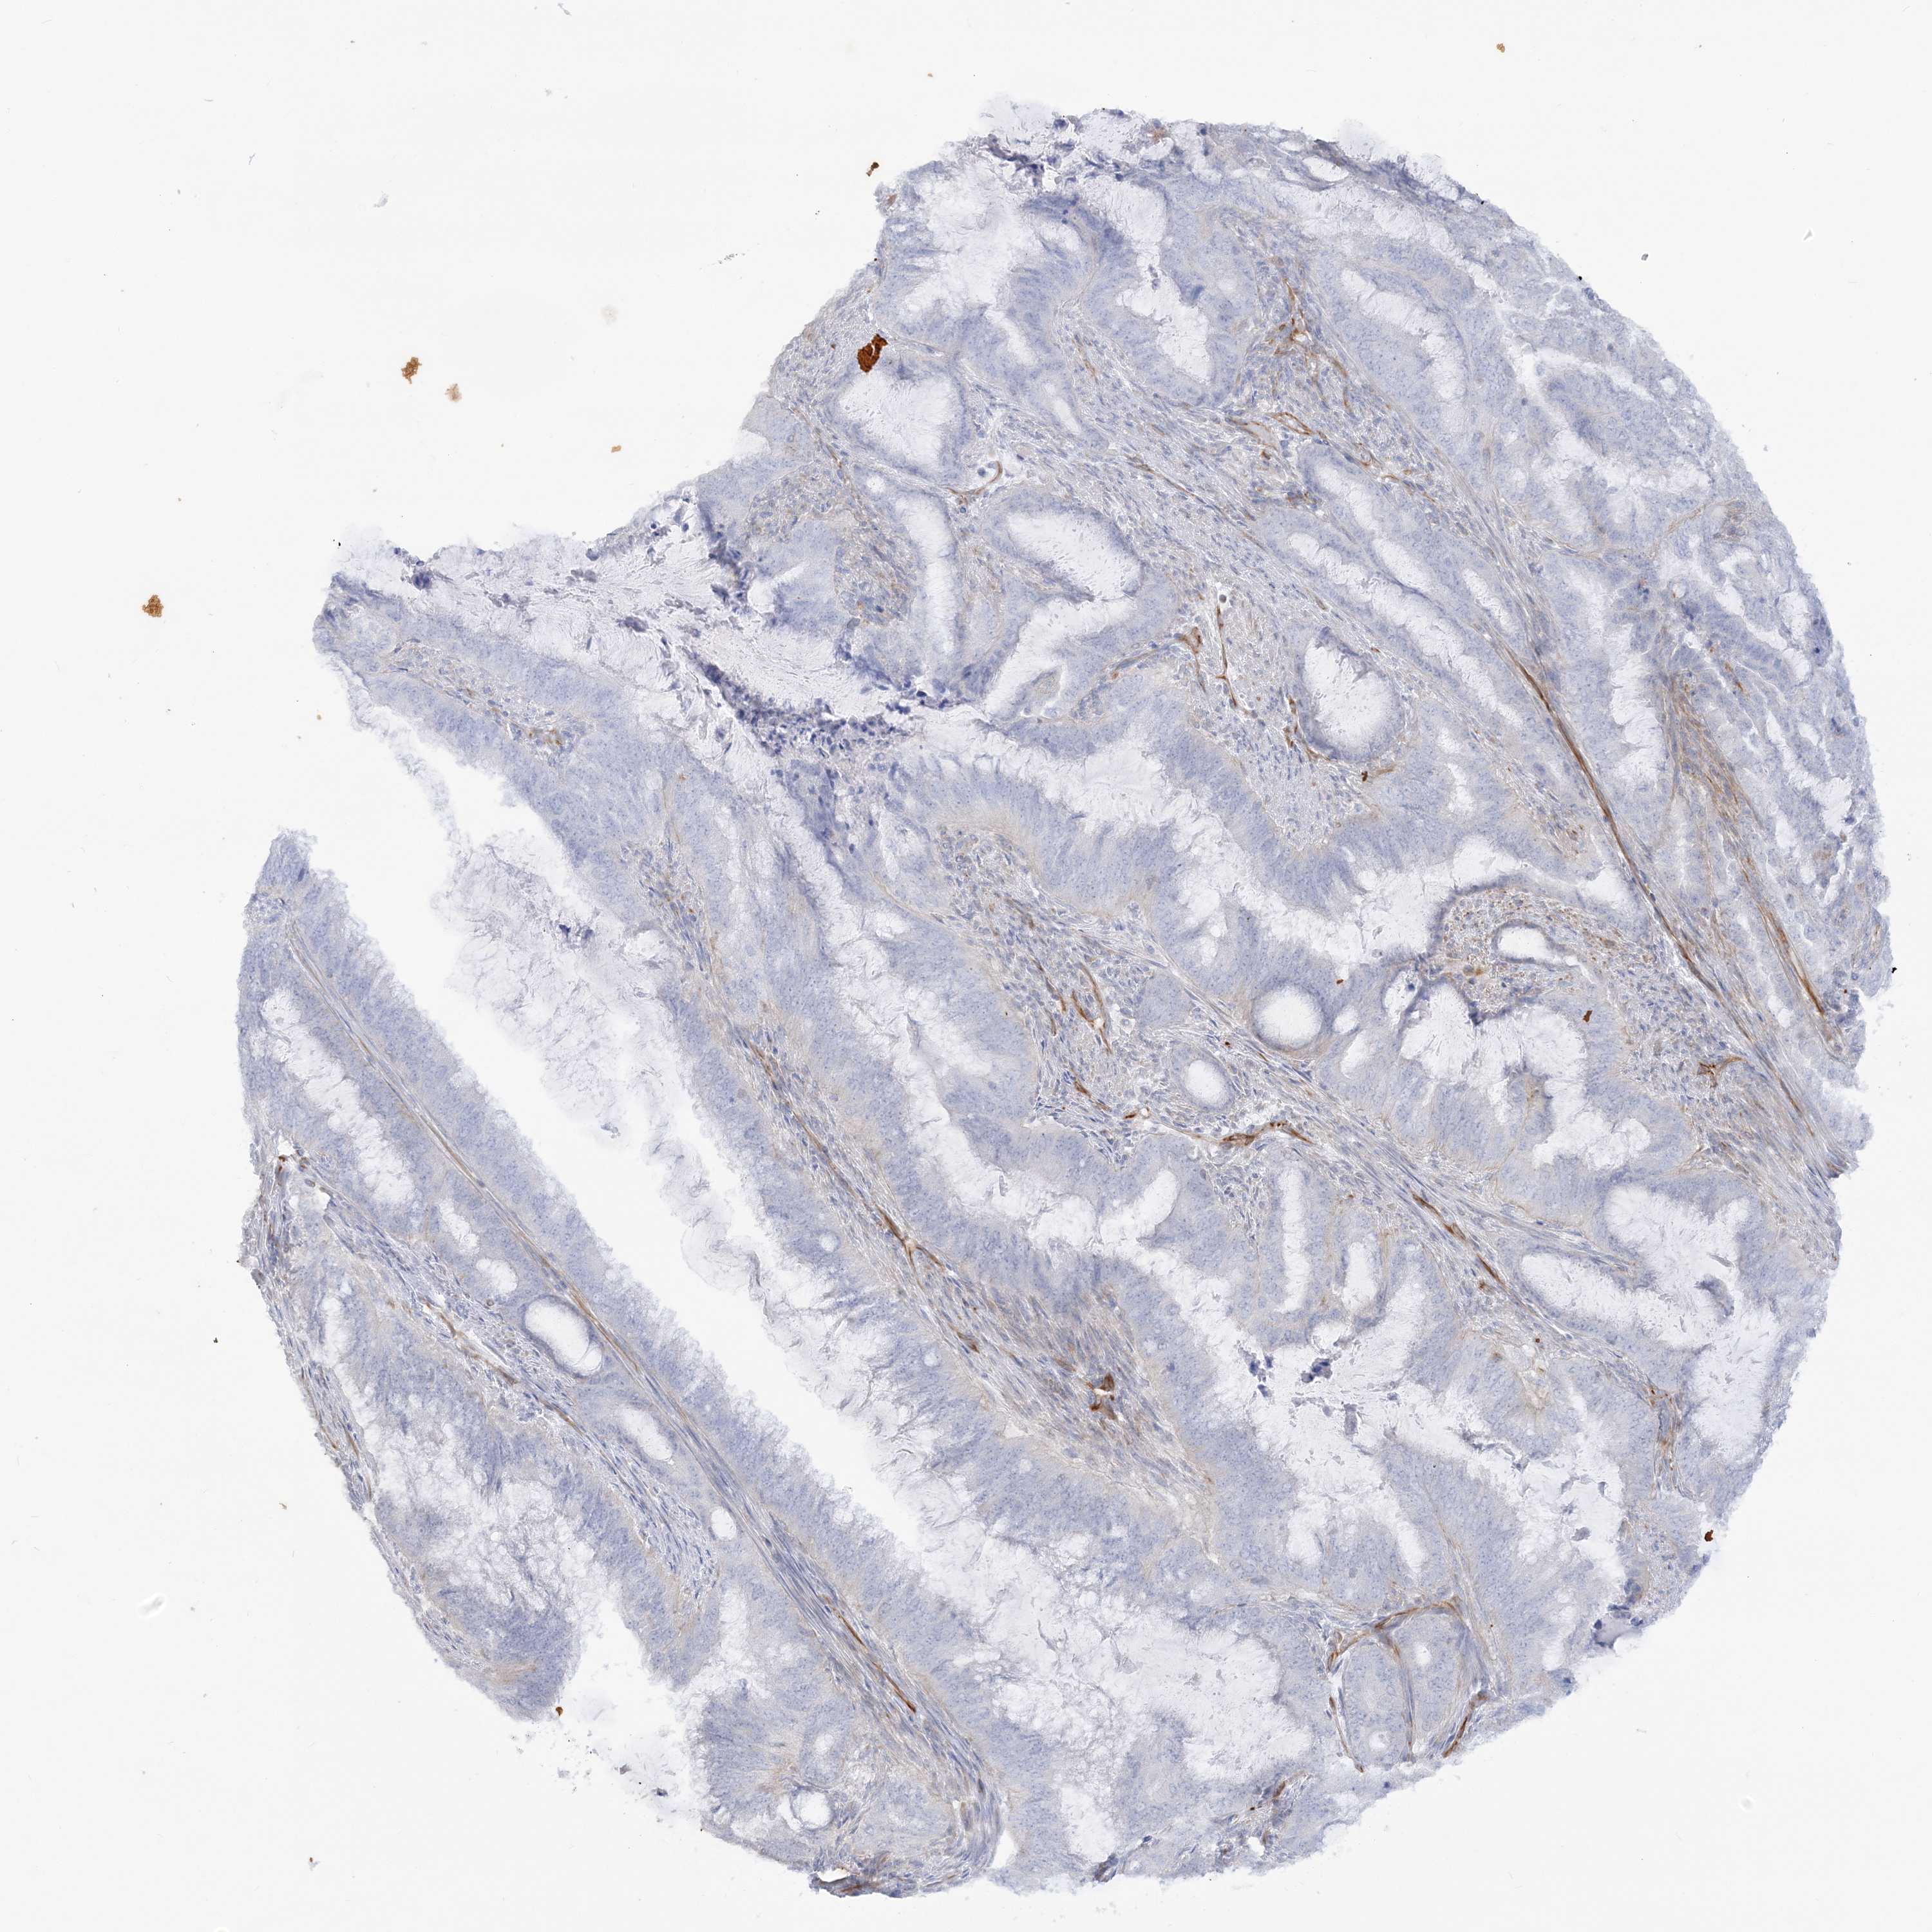

ENDOMETRIAL CANCER - Protein expressioni

A mouse-over function shows sample information and annotation data. Click on an image to view it in a full screen mode. Samples can be filtered based on level of antibody staining by selecting one or several of the following categories: high, medium, low and not detected. The assay and annotation is described here.

Note that samples used for immunohistochemistry by the Human Protein Atlas do not correspond to samples in the TCGA dataset.

Antibody stainingi

Antibody staining in the annotated cell types in the current human tissue is reported as not detected, low, medium, or high, based on conventional immunohistochemistry profiling in selected tissues. This score is based on the combination of the staining intensity and fraction of stained cells.

Each image is clickable and will lead to virtual microscopy that enables deeper exploration of all samples and also displays staining intensity scores, fraction scores and subcellular localization as well as patient and tissue information for each sample.

Antibody HPA036560

Antibody HPA036561

Staining

High

Medium

Low

Not detected

Intensity

Strong

Moderate

Weak

Negative

Quantity

>75%

75%-25%

<25%

None

Location

Nuclear

Cytoplasmic/membranous

Cytoplasmic/membranous,nuclear

Adenocarcinoma, NOS